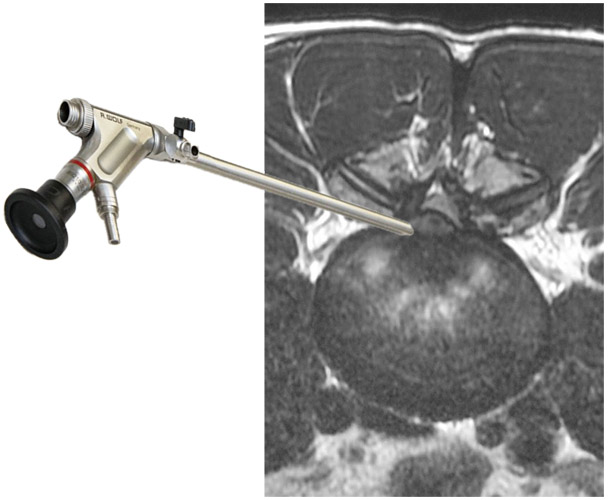

国内で施行されている脊椎内視鏡手術にはいくつかの方法があります。FESSはFull-Endoscopic Spine Surgeryの略称です。そのなかでもヘルニアに対する方法はFED(Full-Endoscopic Discectomyの略称)とも呼ばれます。これまでは、PED(Percutaneous Endoscopic Discectomyの略称)と呼ばれていた方法で、近年名称がFEDに統一化されてきています。カメラを挿入するための8-10mm程度の小さな穴をあけ手術を行います。

FESSに対応可能な手術には腰椎椎間板ヘルニアがあります。また、腰部脊柱管狭窄症や頚椎椎間板ヘルニアの一部の症例にも施行可能です。

(ただしすべての腰椎椎間板ヘルニアに対して可能というわけではありません。担当医にご相談ください。)

FESSの特徴

いままでの脊椎内視鏡にはMEDと呼ばれているものがあり、約16mm径の筒を挿入して、その中で手術操作を行うものでした。体型の大きな方や脊柱のより深いところの治療を行う場合には操作性が悪いことがありました。一方、FESSは8-10mm程度の傷で専用の器械を直接病変部位に挿入し、ヘルニアを切除したり神経組織の圧迫を取り除くことが可能です。手術によって損傷される背中の筋肉は最小限であり、術後の疼痛をできるだけ少なくすることが可能です。そのため、術後早期にリハビリが可能となり、仕事への早期復帰も実現可能です。

FESSで用いられるアプローチ方法

FESSで行う腰椎椎間板ヘルニアの手術には、インターラミナ法(IL法)、トランスフォラミナル法(TF法)などがあります。ヘルニアの発生部位などに応じて最も適した方法を選択します。